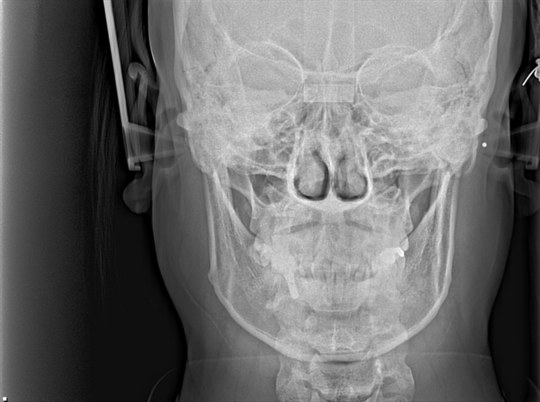

②セファロ

正面

側方

セファロは矯正歯科特有のレントゲンです

正式には『頭部X線規格写真』といいます

撮影する条件が決まっており

名前にあるように『規格』化されています

そのため事前にレントゲン上で角度計測などを行い

歯列矯正後にその角度などを比較することもできます

特に側方のセファロを利用すると

横顔の改善(前歯の前突、口元の突出など)

をデジタルシミュレーションすることも可能です